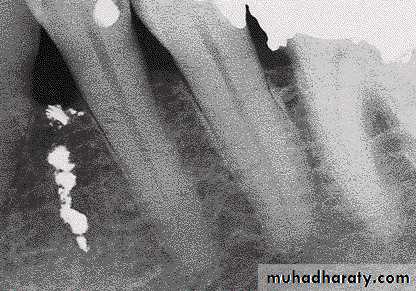

Amalgam tattoos are a result of fragments of the material being embedded in the oral mucosaAmalgam tattoos may be radio-opaque